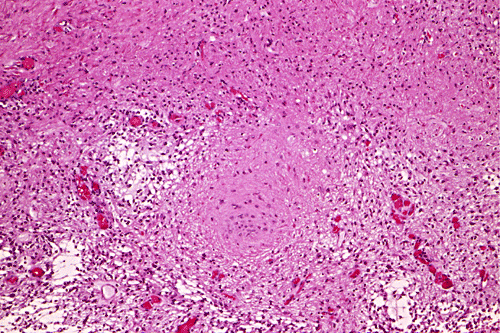

These photos were obtained from the formalin fixed paraffin embedded sections.